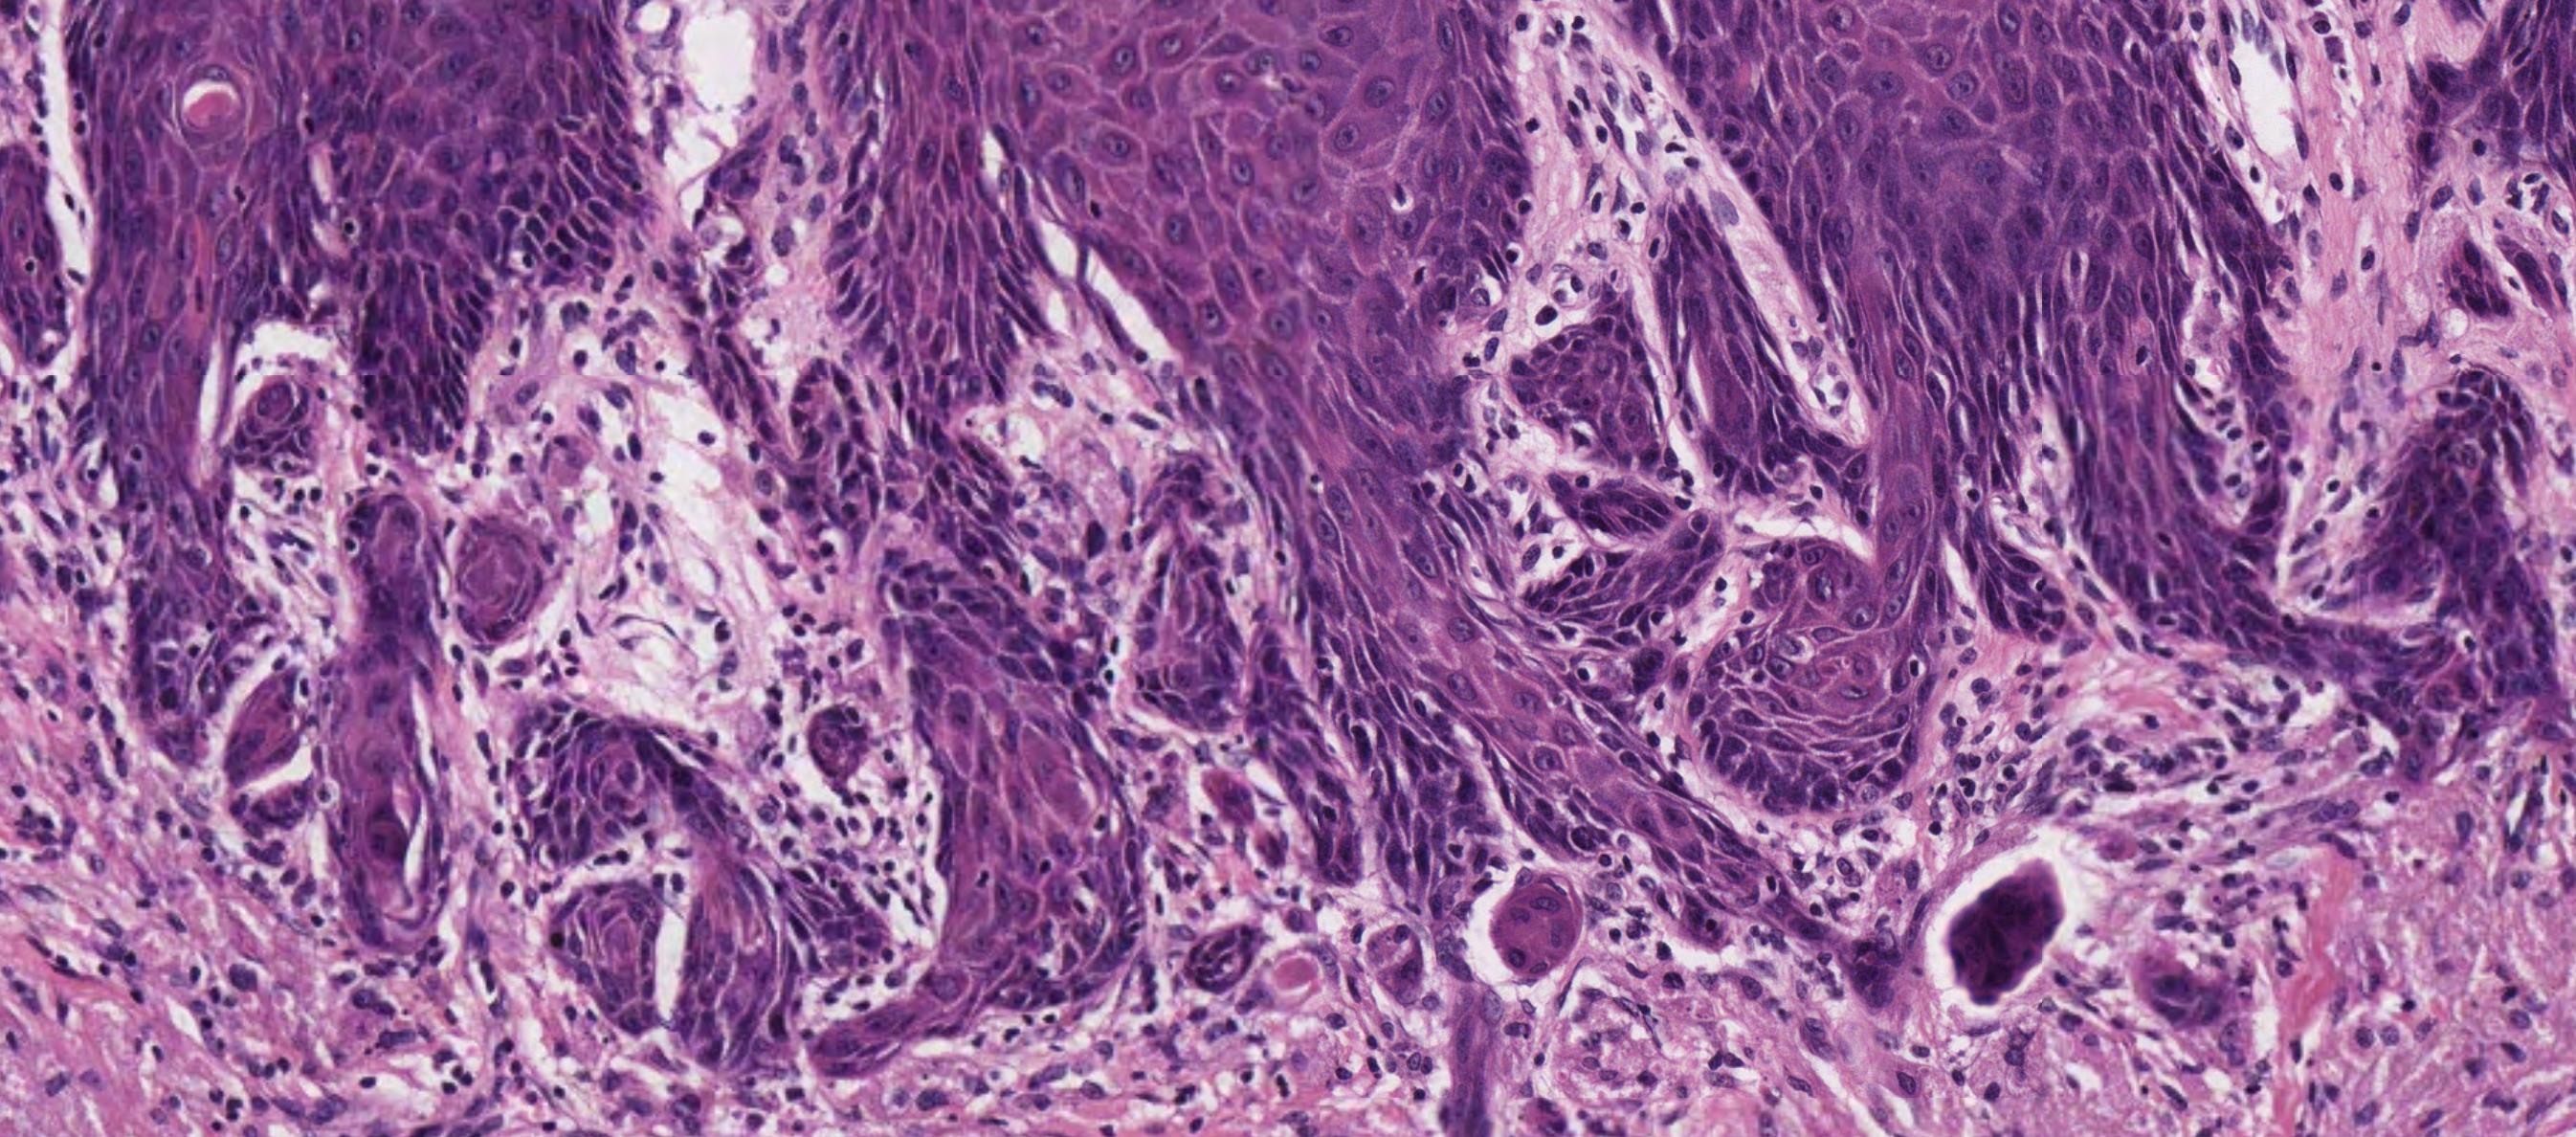

Case 7- Salient points

• SCC • Is lymphoid tissue normal- small monotonous sheets, no follicles • Work up- IHC

??

Case 7 Diagnosis

Squamous

cell

carcinoma

and Lowgrade small cell lymphoma (Grade 1 follicular type NHL)